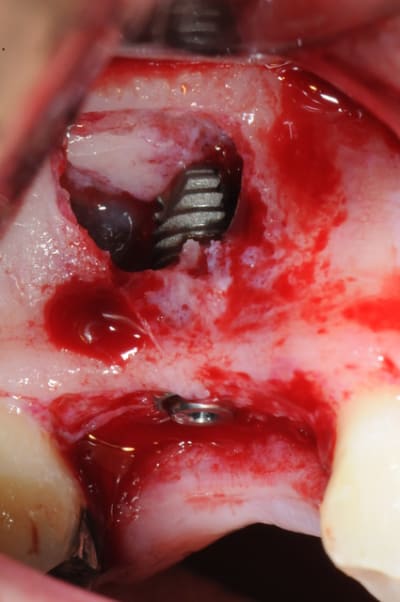

je sais pas si c'est un produit miracle, mais pour les sinus lift, c'est fantastique.

outre le fait de stabiliser un implant dans un sinus type SA4, pas de risque de voir partir le produit comme avec les granules de bioos et autres..

l'autre avantage est de ne pas avoir à mettre de membrane de recouvrement.

je suis donc hyper satisfait du résultat.

jugez plutôt...

quasiment 6 mois entre les deux interventions (sinus lift et mise à jour)

c'est surtout la qualité des trabéculations osseuses qui m'interpelle.

d'habitude, on voit toujours un peu de particules, ici, c'est vraiment top.

Je suis en tout point d'accord avec toi : ce qui est vraiment intéressant, ce sont les trabéculations osseuses obtenues après cicatrisation.

l'application type du VitalOs, avec le bone splitting.

Chapeau gamin c'est très propre et très bien iconographié.

très convaincant Thomas! et les photos toujours bien nettes.

je crois que c'est la première fois que je vois une cliché radio à quelques mois post-op avec ce matériau et le résultat semble excellent.